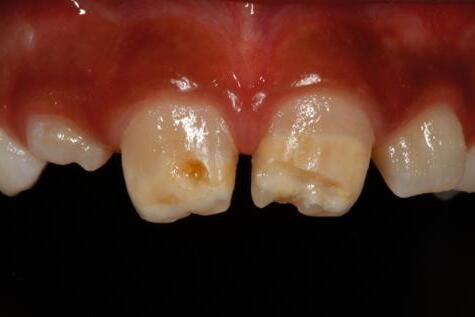

La caries es una enfermedad multifactorial de alta prevalencia que actualmente se trata con un enfoque donde prevalece el concepto de “salud bucal”, “prevención” y “atención oportuna” antes de presentar dolor e incluso la evidencia de la enfermedad, evaluando factores de riesgo como dieta, hábitos, higiene bucal, salud general, entre otros

Se puede presentar Amelogénesis imperfecta, Hipomineralización molar incisivo, Hipoplasia del esmalte y por supuesto Caries dental

Se considera que los pacientes con

Celíaca tienen mayor riesgo de desarrollar defectos del esmalte (50%)